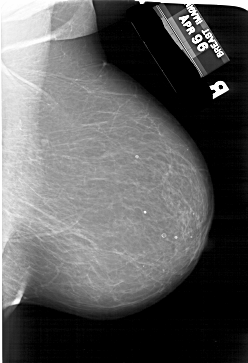

A_1204_1.LEFT_CC

RIGHT_CC LINES 6721 PIXELS_PER_LINE 4366 BITS_PER_PIXEL 12 RESOLUTION 43.5 NON_OVERLAY